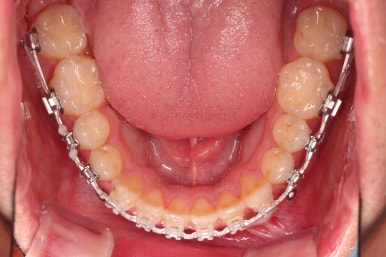

초진 시 입안의 모습입니다.

교합이 많이 안좋습니다.

위아랫니가 서로 엇갈려 가며 지그재그로 껴 들어가야 어금니 맞물림이 생기는데요.

이번 환자분은 아랫니, 아래턱이 전반적으로 앞으로 나와 있어서 교합이 전혀 안되고 있는 상태였습니다.

수술 전 교정과정이 거의 마무리 되어 갑니다.

오히려 앞니가 거꾸로 물리는 정도는 더 심해지고요.

수술 직전이 얼굴모습도 가장 주걱턱이 심한 양상으로 됩니다.